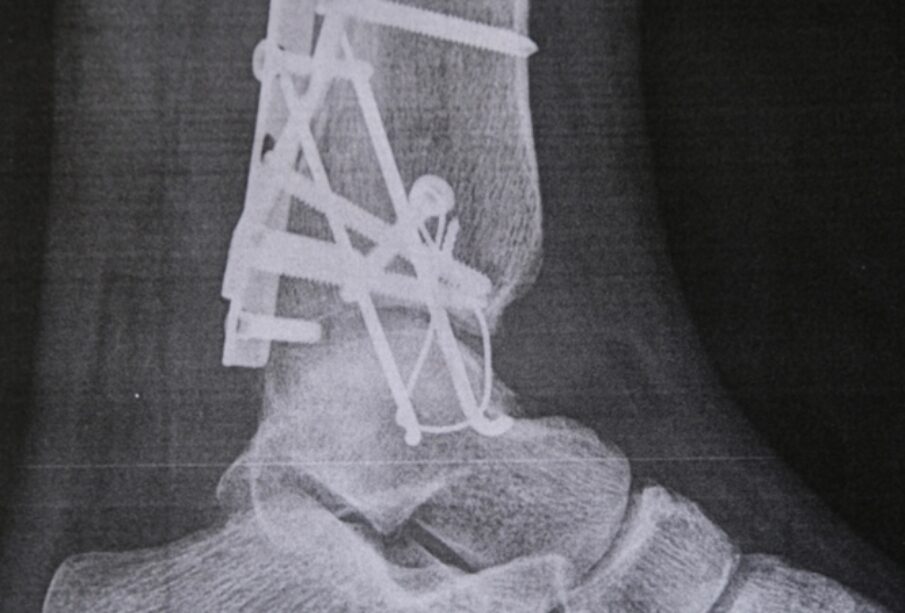

- Nugaros ir kitų sąnarių (klubų, kelių, pečių, čiurnų) skausmai bei sąstingis.

- Stuburo deformacijos, laikysenos pokyčiai.

- Sunkesniais atvejais – stuburo slankstelių suaugimas (ankilozė), žymiai apsunkinantis judesius.